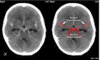

Which arteries do the arrows point to? [1]

Lenticulostiate arteries

Q